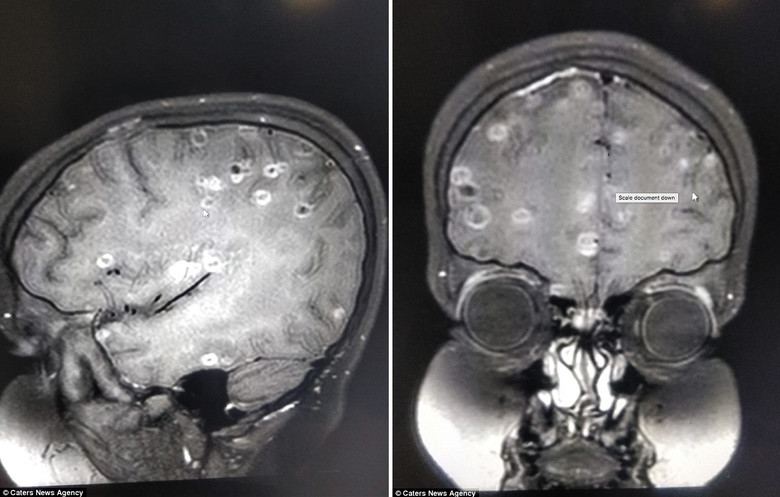

У восьмилетней девочки в Индии врачи обнаружили более 100 личиночных капсул свиного цепня — возбудителя, приводящего к цистицеркозу. Паразиты оказались в мозге, что квалифицируется как нейроцистицеркоз и объяснило внезапные эпилептические припадки у ребёнка.

Сначала состояние ребёнка расценили как обычную кисту головного мозга и назначили высокие дозы стероидов, но лечение не давало ожидаемого эффекта. После дополнительного обследования специалисты установили, что киста на деле содержит личинки свиного цепня — паразита, которому человеком бывает конечный хозяин.

Сибирский цепень, или свиной цепень, чаще передаётся через плохо приготовленную свинину, но заразиться можно и бытовым путём: немытые руки, загрязнённые яйца паразита, или немытые фрукты и овощи. Когда личинки попадают в организм и мигрируют в мозг, они вызывают нейроцистицеркоз — одну из серьёзных причин судорожных расстройств и неврологических нарушений у детей и взрослых.

В зависимости от локализации и стадии цистицерков в головном мозге клиника может варьироваться от головных болей и судорог до нарушений зрения и когнитивных функций. Лечение обычно включает противогельминтные препараты, иногда хирургическое вмешательство и симптоматическую терапию против судорог и воспаления.